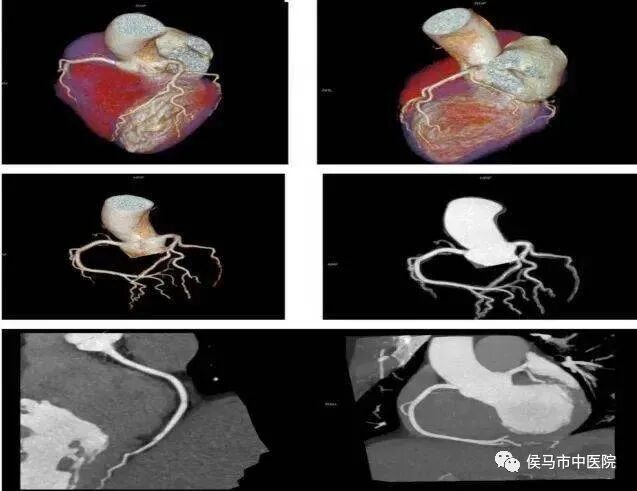

1、 冠状动脉CTA

冠状动脉CTA在检查冠状动脉有无狭窄及其他病变、冠状动脉支架植入后评价、搭桥术前计划和术后评价具有极大的优越性。实现冠状动脉的无创检查,它反映血管狭窄程度及各种血管病变,为冠心病的筛选普查及诊断提供了一种安全、迅速的检查方法,更有利于临床各类心血管疾病的诊断。